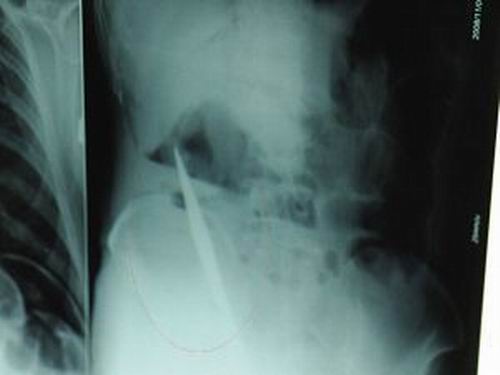

X光片上,尖刀清晰可見。

從男子體內(nèi)取出的尖刀足足有19厘米長(zhǎng)。

昨天(11月6日)上午,記者在徐州礦務(wù)集團(tuán)總醫(yī)院重癥監(jiān)護(hù)室見到了這名男子,目前他雖然已經(jīng)恢復(fù)了意識(shí),但還不能開口說(shuō)話,需要呼吸機(jī)輔助呼吸。據(jù)醫(yī)生介紹,4日中午12時(shí)左右,這名男子因服毒輕生被緊急送到醫(yī)院進(jìn)行搶救,之前,這名男子已經(jīng)在當(dāng)?shù)剜l(xiāng)鎮(zhèn)醫(yī)院進(jìn)行了近20小時(shí)的治療,但效果不佳。“病人被轉(zhuǎn)院到礦總院時(shí)已神志不清,血壓極低,處于休克狀態(tài)。”救護(hù)人員給男子洗胃、初步處理以后,發(fā)現(xiàn)男子呼吸急促,于是趕緊給他拍片檢查。結(jié)果讓所有的醫(yī)生大吃一驚,竟有一把尖狀異物橫在該男子腹腔內(nèi)!當(dāng)天下午5時(shí)30分,輕生男子被推上了手術(shù)臺(tái)。經(jīng)過(guò)40多分鐘的手術(shù),該男子腹腔被打開,手術(shù)醫(yī)生發(fā)現(xiàn),男子體內(nèi)的金屬狀異物竟然是一把長(zhǎng)19厘米的尖刀!